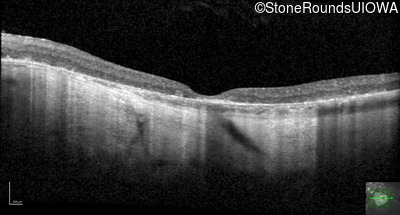

Optical Coherence Tomography - Left - 20/20 -1

Exemplar / OCT Stack